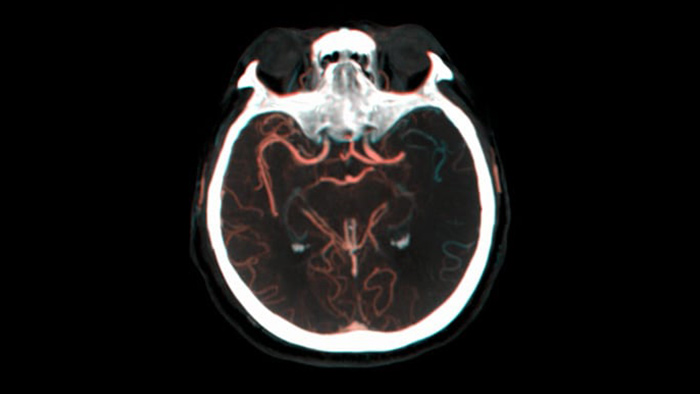

SmartCT Soft Tissue выполняет КТ-подобную визуализацию мягких тканей и дополняет диагностику инсульта тремя способами. Технология бесконтрастного сканирования помогает выявить ишемические изменения на ранних стадиях. Сканирование ранней фазы помогает определить проксимальную окклюзию. Сканирование поздней фазы с усилением контраста направлено на обнаружение коллатералей.

Технология Dual View для одновременного просмотра ранней и поздней фаз КТ-подобной визуализации способствует определению ишемической полутени и обеспечивает визуализацию наполнения коллатералей.

Используйте изображения, полученные с помощью SmartCT (КТ-подобные), с решением Neurovascular Suite, чтобы убедиться в успешности лечения и осуществить проверку на наличие кровотечений.